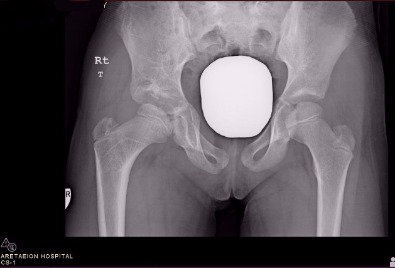

Προεγχειρητικές ακτινογραφίες κοριτσιού ηλικίας τρεισήμιση ετών στην Κύπρο, που παρουσιάστηκε με χολώτητα λόγω συγγενούς εξάρθρωσης του δεξιού ισχίου

Οι πιο πρόσφατες μετεγχειρητικές ακτινογραφίες (4 χρόνια αργότερα) μετά από ανοικτη ανάταξη και οστεοτομίες μηριαίου και λεκάνης. Η ασθενής έχει φυσιολογικό βάδισμα